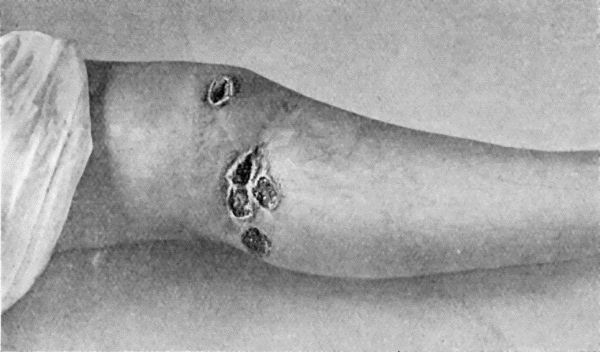

35.Tuberculous Sinus injected through its opening in the Forearm with Bismuth Paste 144

36.Spirochæte pallida 147